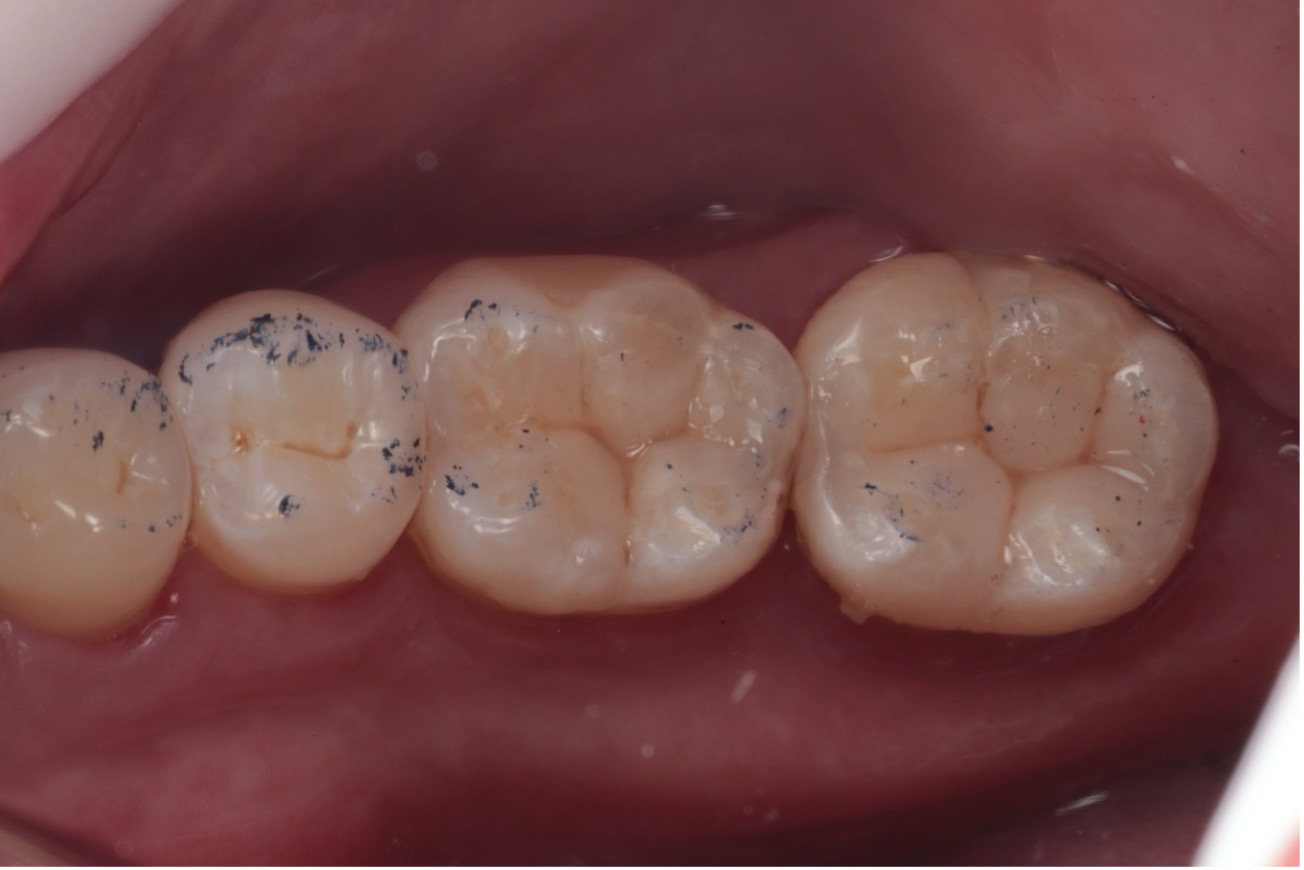

O acabamento e polimento iniciais foram realizados com pontas de borracha Espirais e escova de pelo de cabra, promovendo brilho e lisura à superfície (Figura 11). Após a remoção do isolamento, realizou-se o ajuste oclusal dinâmico e estático (Figura 12).

Figura 12 – Ajuste oclusal